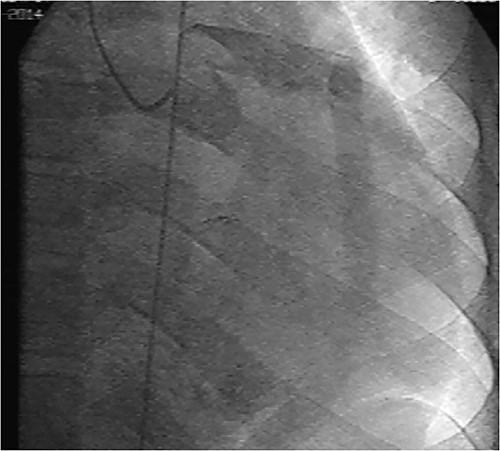

Initial physical examination showed stable vital signs. Auscultation found systolic murmurs of mitral and tricuspid regurgitations. There were no peripheral edema or other signs of heart failure. Abdominal examination revealed no tenderness, hepatomegaly or ascites. Electrocardiogram at admission showed sinus rhythm with no conduction abnormalities or signs of ischemia. Chest radiograph found an enlargement of the cardiac silhouette. Routine blood tests were normal. Transthoracic echocardiography (TTE) found a bi-atrial cystic structure, which we initially suspected to be a hydatid cyst as cystic echinococcosis is highly endemic in Morocco. Color Doppler showed a massive shunt with blood coming into the right atrium (RA) from an unknown source (Fig. 1). Cardiac magnetic resonance imaging (CMR) showed a bilobed cystic lesion hypointense on T1 and T2 sequences, with the same signal as cardiac chambers, located below and behind the left atrium (LA). The superior lobe was 48-mm wide and the inferior lobe 65-mm wide. On the peripheral wall of this structure, a giant circumflex artery (LCX), with a right atrial shunt, was present (Fig. 2). Coronary angiography (CA) along with computed tomography angiography (CCTA) confirmed the bilobed circumflex saccular aneurysm and CAF (Figs 3 and 4).